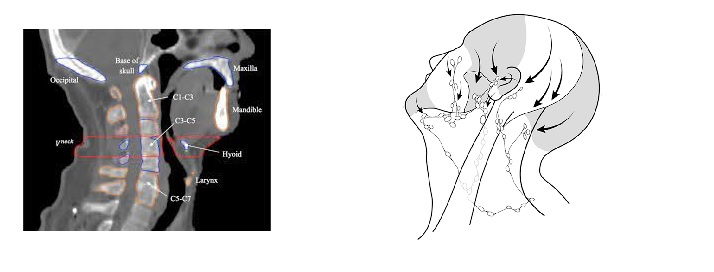

15th of December 2014 a Monday. I was initially diagnosed of 14th of February 2014 with Stage 4 Hodgkins Lymphoma, my initial chemotherapy ABVD was at a very aggressive level, it had worked to a substantial degree but not 100%, 99% in blood cancer is not enough. A decision to use an extreme level of Targeted Radiotherapy was made. The targeted area was to the right side of my neck, covering roughly 4 inches square to include the back of my throat. I had an exposure of 40gm/grey which was 4gm above maximum level of exposure for that part of the body. The 4 weeks were hard, harder than the previous six months of Chemotherapy. My skin was badly burnt in the area exposed, the treatment damaged nerves in the area beyond repair. The damage was caused by exposure to radiation.